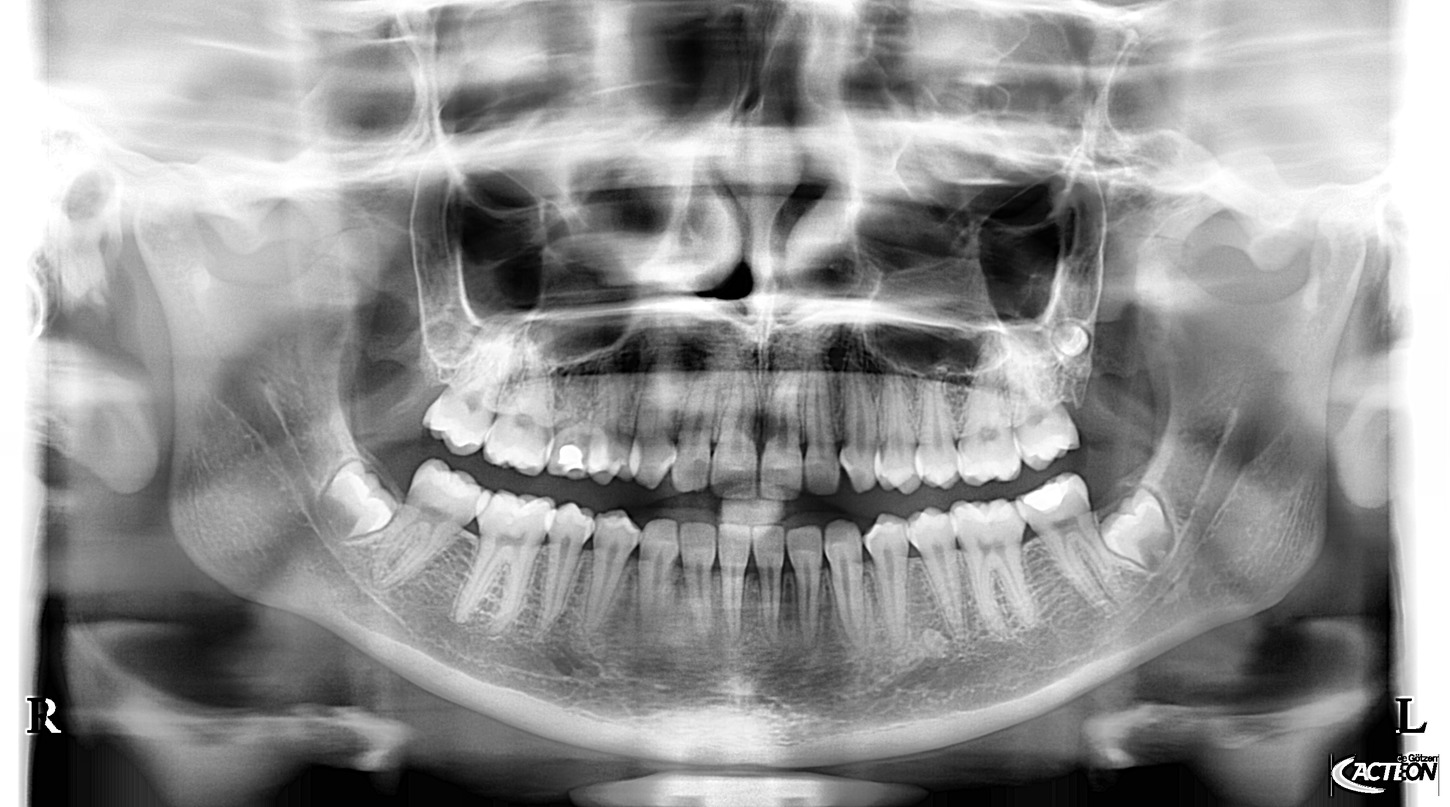

Přesné snímky pro zlepšení diagnostiky. To přináší panoramatické RTG od dodavatele Acteon Satelec, které jsou svými parametry a cenovou dostupností nejlepší volbou pro stomatologické praxe. Volit můžete z mnoha variant (kotvení, rozšiřitelnost o 3D, rozšiřitelnost o kefalometrické rameno atd.) a tím jsou snadno přizpůsobitelné do každého prostoru a každé stomatologické praxe. Jedná se o OPG, která svou kvalitou a ovládáním předčí všechna očekávání a řadí se tak mezi nejpoužívanější OPG na světovém i českém trhu. Poskytuje veškeré panoramatické možnosti pro všeobecnou stomatologii: dentální panoramatickou, klouby i sinusy. Jednoduché nastavení, pohodlí pacienta a rychlé vyšetření. Společnost Fénix Dental dodává všechny přístroje s odborným zaškolením, a to dle individuální potřeby každého uživatele. Díky Aies SW je zobrazení OPG snímků bezkonkurenční. Díky panoramatickému RTG od výrobce Acteon, získáte nejpřesnější diagnostickou hodnotu, která snese i ta nejpřísnější měřítka. Společnost Fénix Dental je přímý zástupce a autorizovaný servis pro produkty Acteon. Prohlédněte si naši nabídku právě zde a neváhejte nás kontaktovat pro bližší informace.